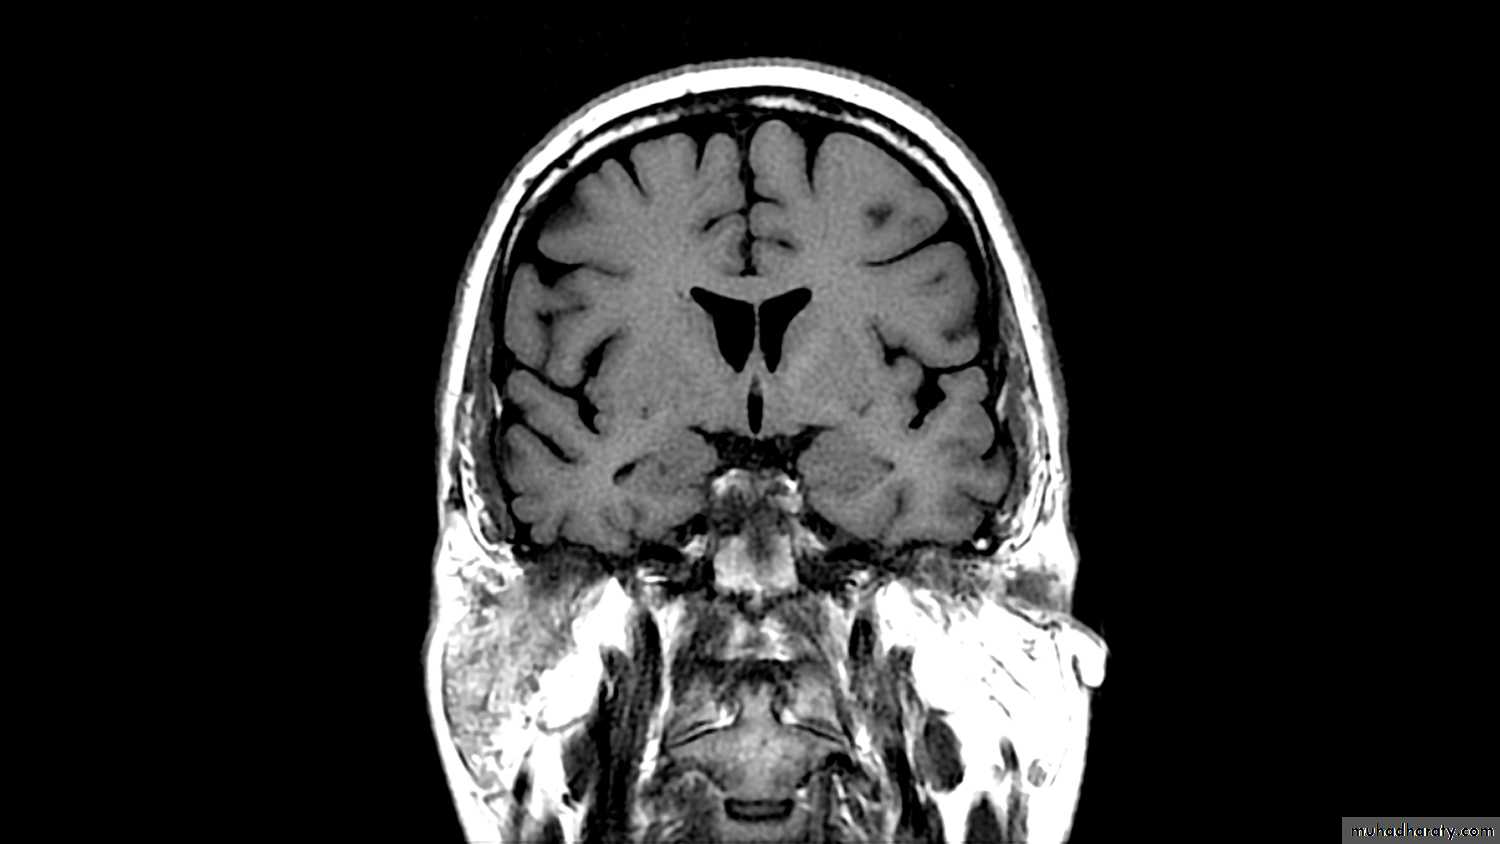

Ventricles

Lateral

Third

Fourth

Flow of CSF:

• The CSF passes from the lateral ventricles (I and II) through the foramen of Monro into the third ventricle (III) then through the aqueduct of Sylvius into the fourth ventricle (IV) and out into the subarachnoid space through the foramina Lushka & Magendie .Absorption of CSF